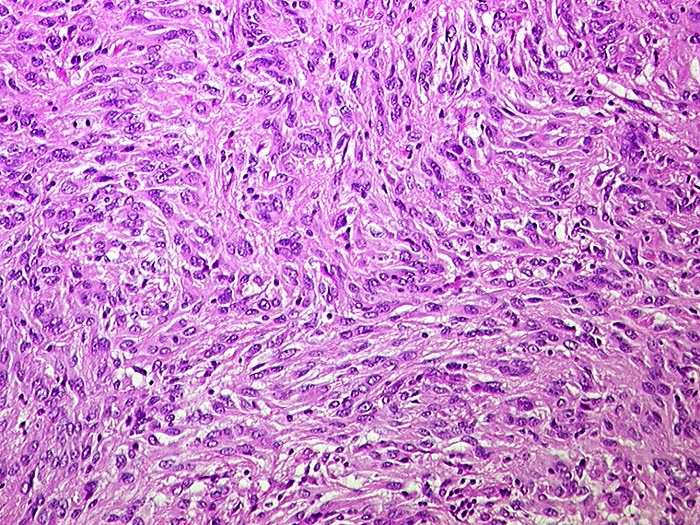

Gastrointestinaler Stromatumor (GIST)

maligner Tumor

Dünndarm

Zellreicher mesenchymaler Tumor. Die spindeligen Tumorzellen zeigen geringgradige Atypien und bilden kleine Stränge mit unregelmässigem Verlauf.

Metastasen im mesenterialen Fettgewebe und in der Serosa. S-100 negativ, SM-Actin herdförmig positiv, CD 117 (c-kit) positiv.

Histologie